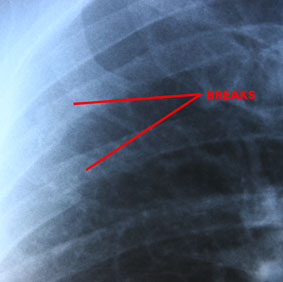

The First X-Ray

To cut a long story sort (it included at lot of me whimpering), I went through the A&E dept at Royal Darwin hospital culminating with the doctor slapping my X-Rays onto those light boxes like they do on the telly.  Looking over his shoulder, I just went “Ohhhhh Shit!”  Even I could see two very clearly broken ribs.  Not just cracked, but clean breaks.  They’re ribs 3 & 4, just under the shoulder blade – and they hurt.